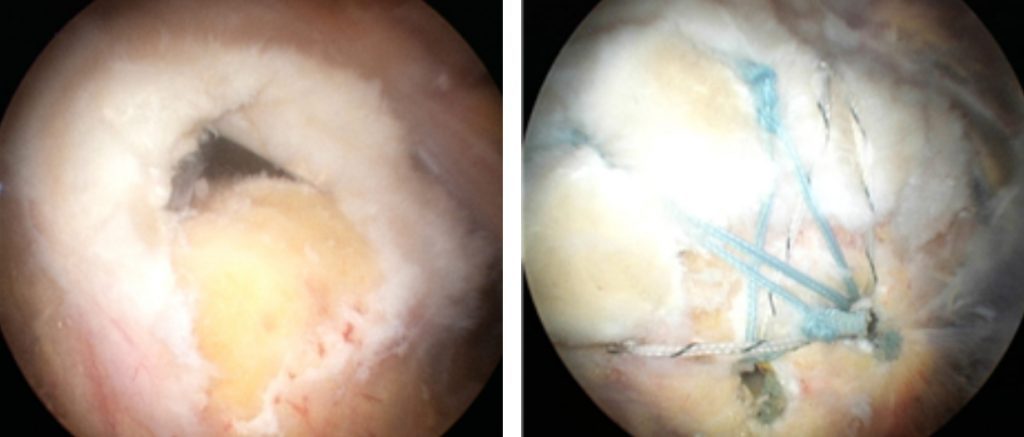

수술은 관절내시경을 통해 진행되며 연골판 상태에 따라 부분 절제술과 부분술로 나뉘게 됩니다.

치료를 위해서는 카메라가 들어간 반대편으로 추가적인 절개를 통하여 기구를 삽입하여 다듬거나 봉합하는 등 치료가 이루어집니다.

관절내시경ㅇㅇ-1024x437.jpg 바른신경외과 회전근개파열 수술

예를 들어 반월상 연골판 수술의 경우

찢어진 부분을 다듬는 부분 절제술은 수술 시간은 약 30분 내외로 소요되며 회복 속도가 빠르며 환자에 따라 다음날 바로 퇴원할 수 있습니다. 일상적인 보행 또한 수술 후 다음날부터 가능하지만 붓기나 통증이 남아있기 때문에 안정기까지 2주 정도 소요됩니다.

찢어진 부분을 봉합하는 봉합술의 경우 위치에 따라 달라질 수 있지만 수술시간 약 1시간 내외로 소요됩니다.

회복은 4주에서 6주 정도의 고정 기간이 필요하고 보행 시 최대한 체중 부하가 닿지 않도록 해야 합니다. 이후 깁스 치료와 단계적으로 관절 운동 치료를 통해 호전을 기대할 수 있습니다.

바른신경외과 반월상 연골 파열 수술